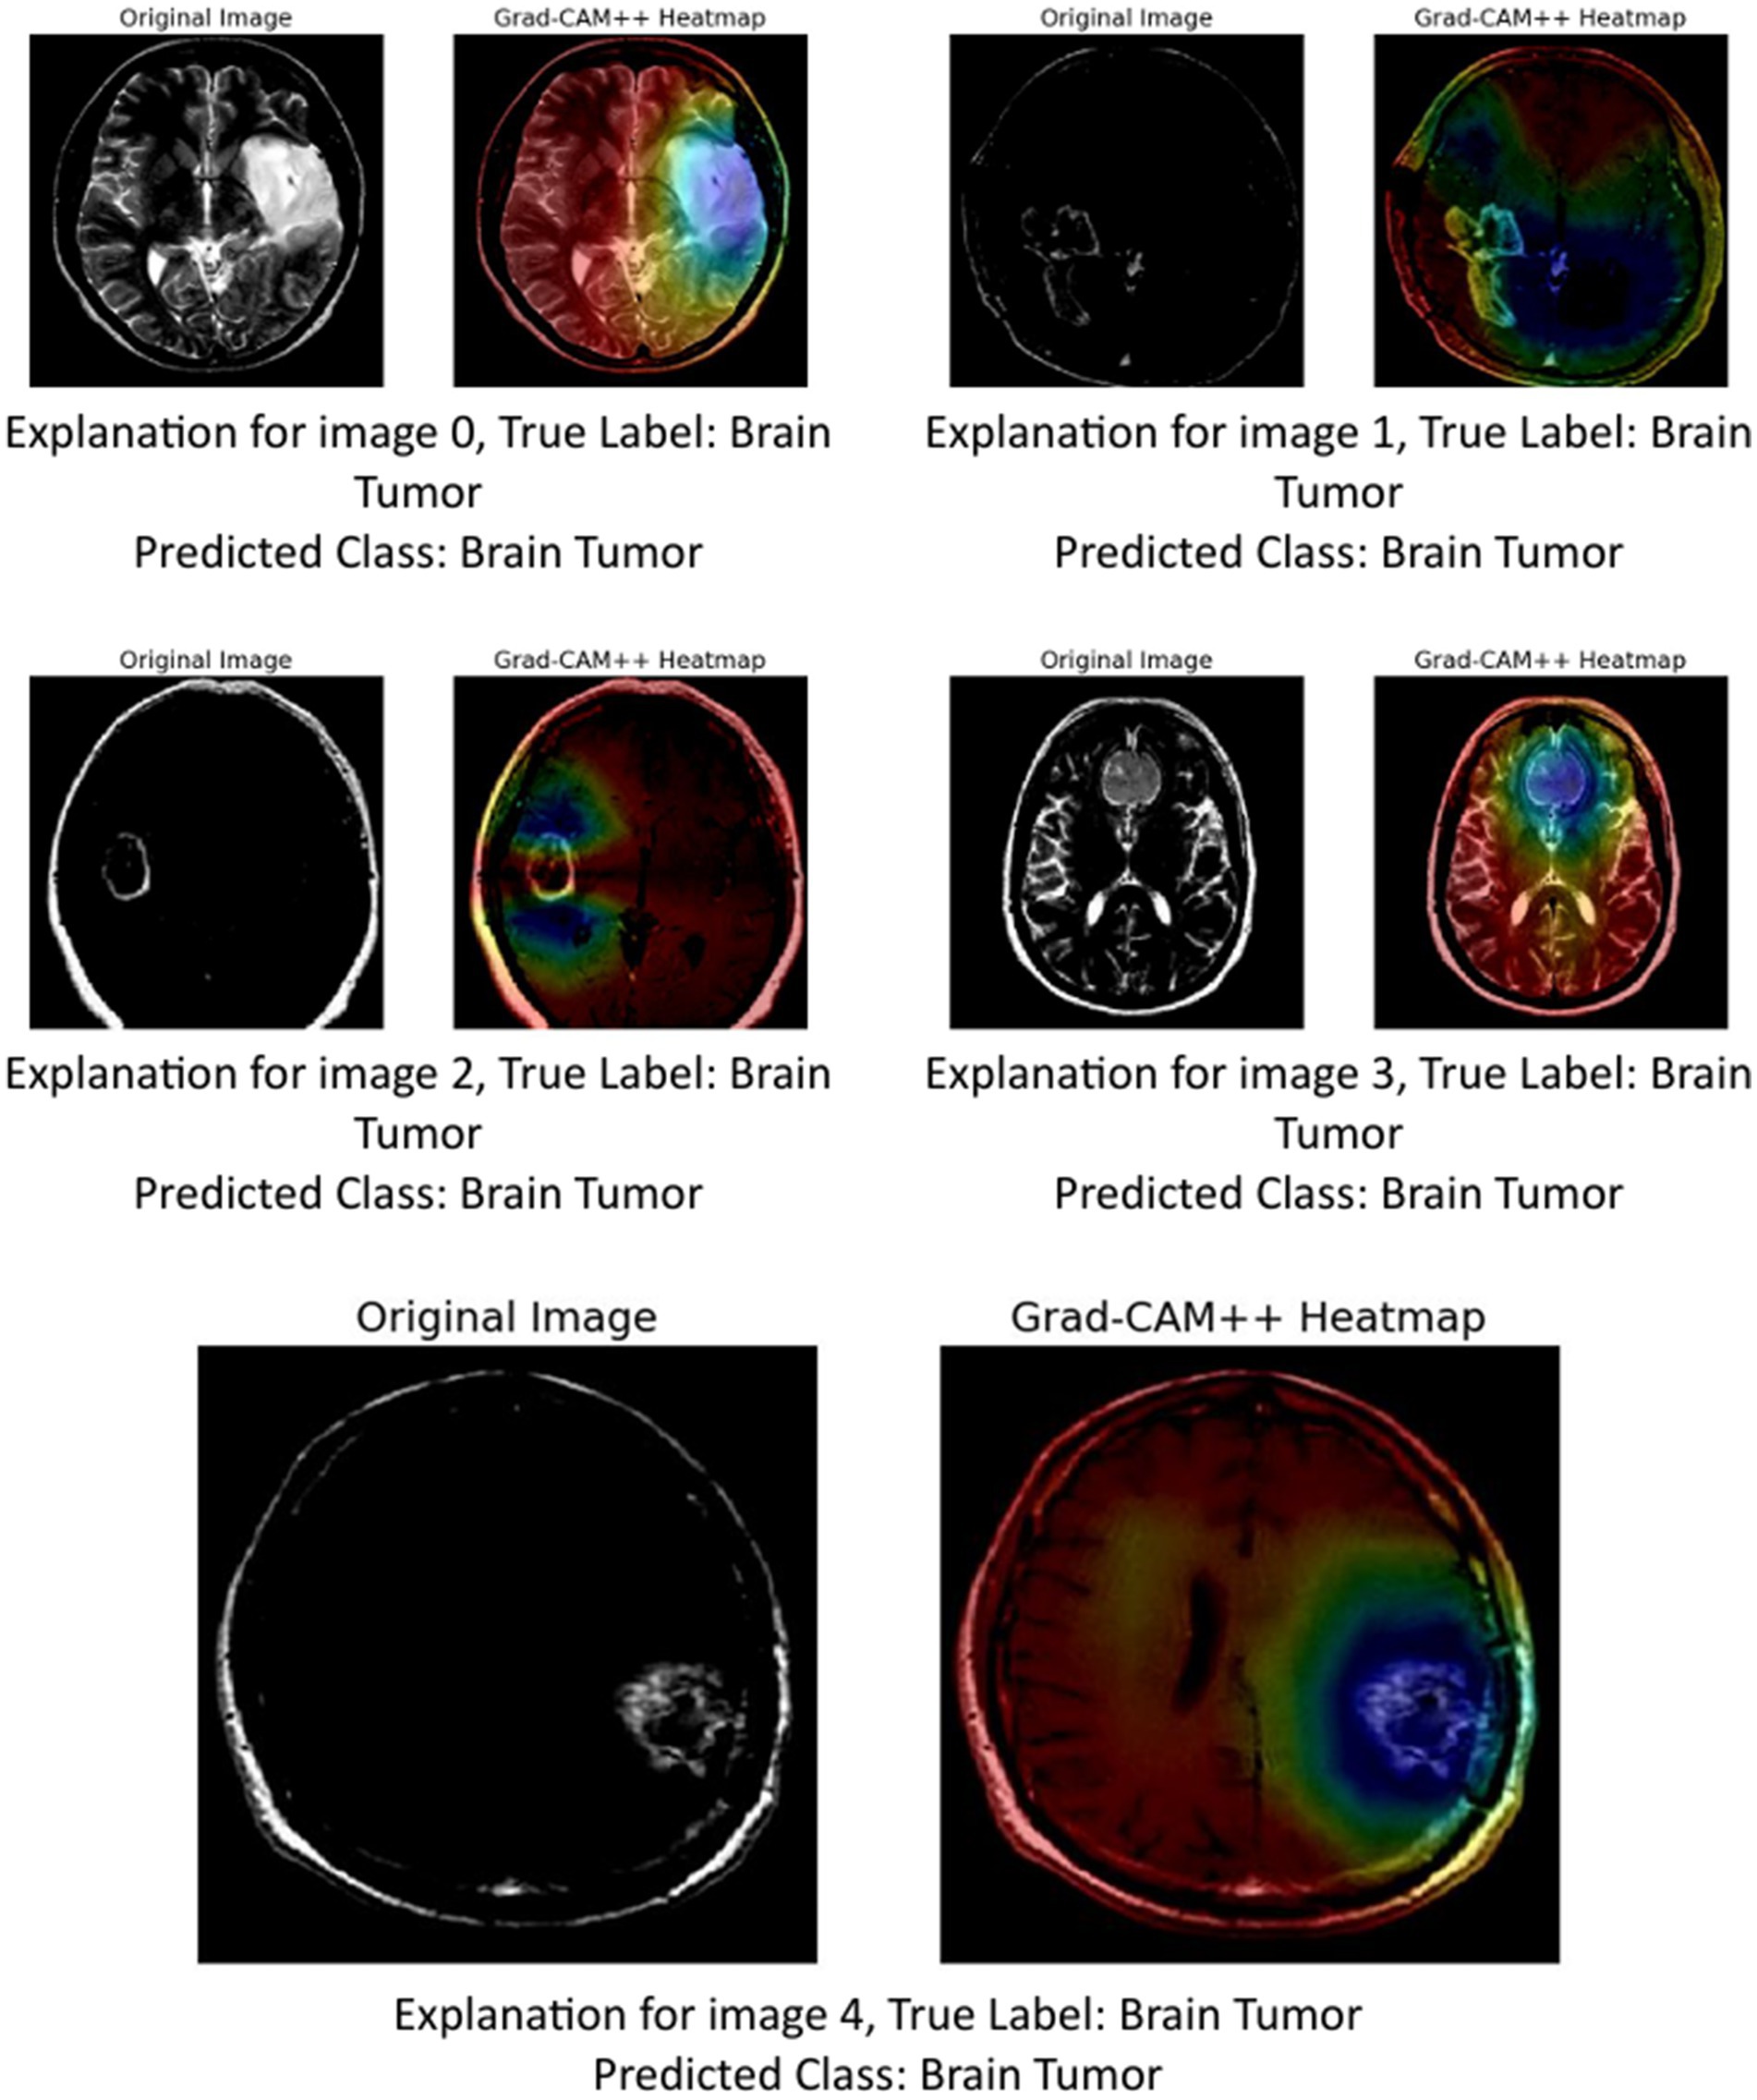

5.1.3 GRAD-CAM++

The provided image set presents a series of Grad-CAM++ visualizations applied to five brain MRI scans, who each diagnosed as having a brain tumor. These visualizations serve as an interpretability tool to understand the internal workings of deep learning models used in medical imaging. Grad-CAM++ (Gradient-weighted Class Activation Mapping++) is an enhancement over the original Grad-CAM technique, offering finer and more spatially precise localization of features that influence a model’s decision.

Grad-CAM++ improves upon Grad-CAM by considering higher-order derivatives of the output can coming the feature maps. This results in sharper and more reliable heatmaps, especially useful when multiple instances or small objects are present in an image (Chattopadhyay et al., 2022). In the context of medical imaging, such as MRI scans of brain tumors, Grad-CAM++ helps visualize which exact regions of the scan the model deems important for classification (Gao et al., 2023).

-

Image 0:

Original image: Displays a clear structure of the brain, including the tumor area.

Grad-CAM++ heatmap: The central region, where the tumor is visibly located, shows a high activation (in red-yellow), indicating that the model strongly relied in this area to identify the tumor.

Observation: The tumor boundary and surrounding tissue are highlighted effectively, demonstrating good interpretability.

Image 1:

Original image: Features a darker scan, but the tumor is discernible.

Grad-CAM++ heatmap: Activations are concentrated around the upper-mid portion of the brain, aligning well with the tumor location.

Observation: The model captures both the core of the tumor and some adjacent regions, suggesting sensitivity to contextual features.

Image 2:

Original image: A clean scan with a bright abnormal region.

Grad-CAM++ heatmap: Strong focus in the central part, slightly diffused around the tumor area.

Observation: Grad-CAM++ shows focused activation, but also includes surrounding regions, possibly indicating model consideration of surrounding tissues.

Image 3:

Original image: Exhibits distinct brain anatomy with a visible lesion.

Grad-CAM++ heatmap: High intensity near the center with tight boundary focus, particularly over the tumor.

Observation: Suggests that the model is highly accurate in pinpointing tumor locations, confirming the reliability of its internal decision logic.

Image 4:

Original image: Displays a well-formed tumor in the lower right area.

Grad-CAM++ heatmap: The highest activation is located precisely over the tumor mass, with minimal distraction in other areas.

Observation: The result here shows a nearly perfect match between the medical region of interest and the model’s focus.

These visualizations demonstrate (Figure 13) that Grad-CAM++ offers high-resolution, interpretable insights into CNN-based tumor detection models. It not only reveals the correct regions of interest (ROIs) within the MRI scans but also provides medical professionals with a visual validation of model predictions, which is essential for building trust in AI-assisted diagnostics. The consistent overlap between activated areas in the heatmaps and the actual tumor locations supports the use of Grad-CAM++ as a credible explainability method in medical imaging research.

Figure 13

GRAD-CAM++ visualization.